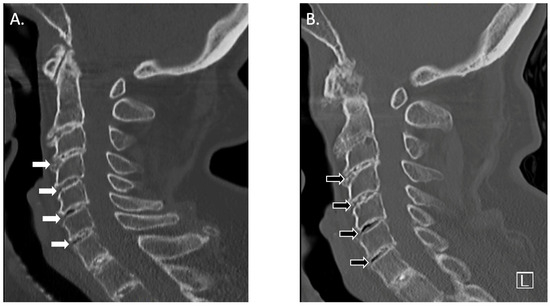

2. Case Report